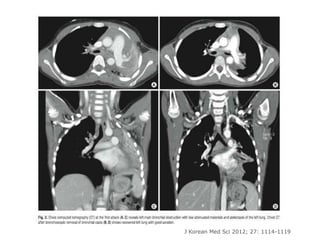

J Korean Med Sci 2012; 27: 1114-1119